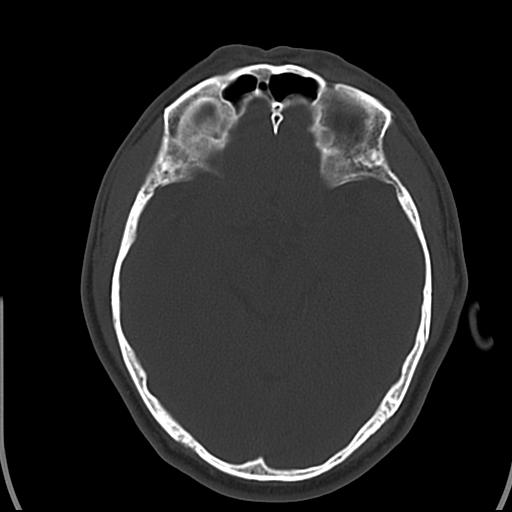

头皮下高密度结节影???临床上在老年男性比较常见。大家看看是什么?成因是? 本例患者,男性,51岁。外伤来诊。无染发史及发根植入史。

考虑异物。

皮下钙化点

没见过,可能为毛囊钙化。

考虑钙化。

这种东西有时要结合触诊和望诊。